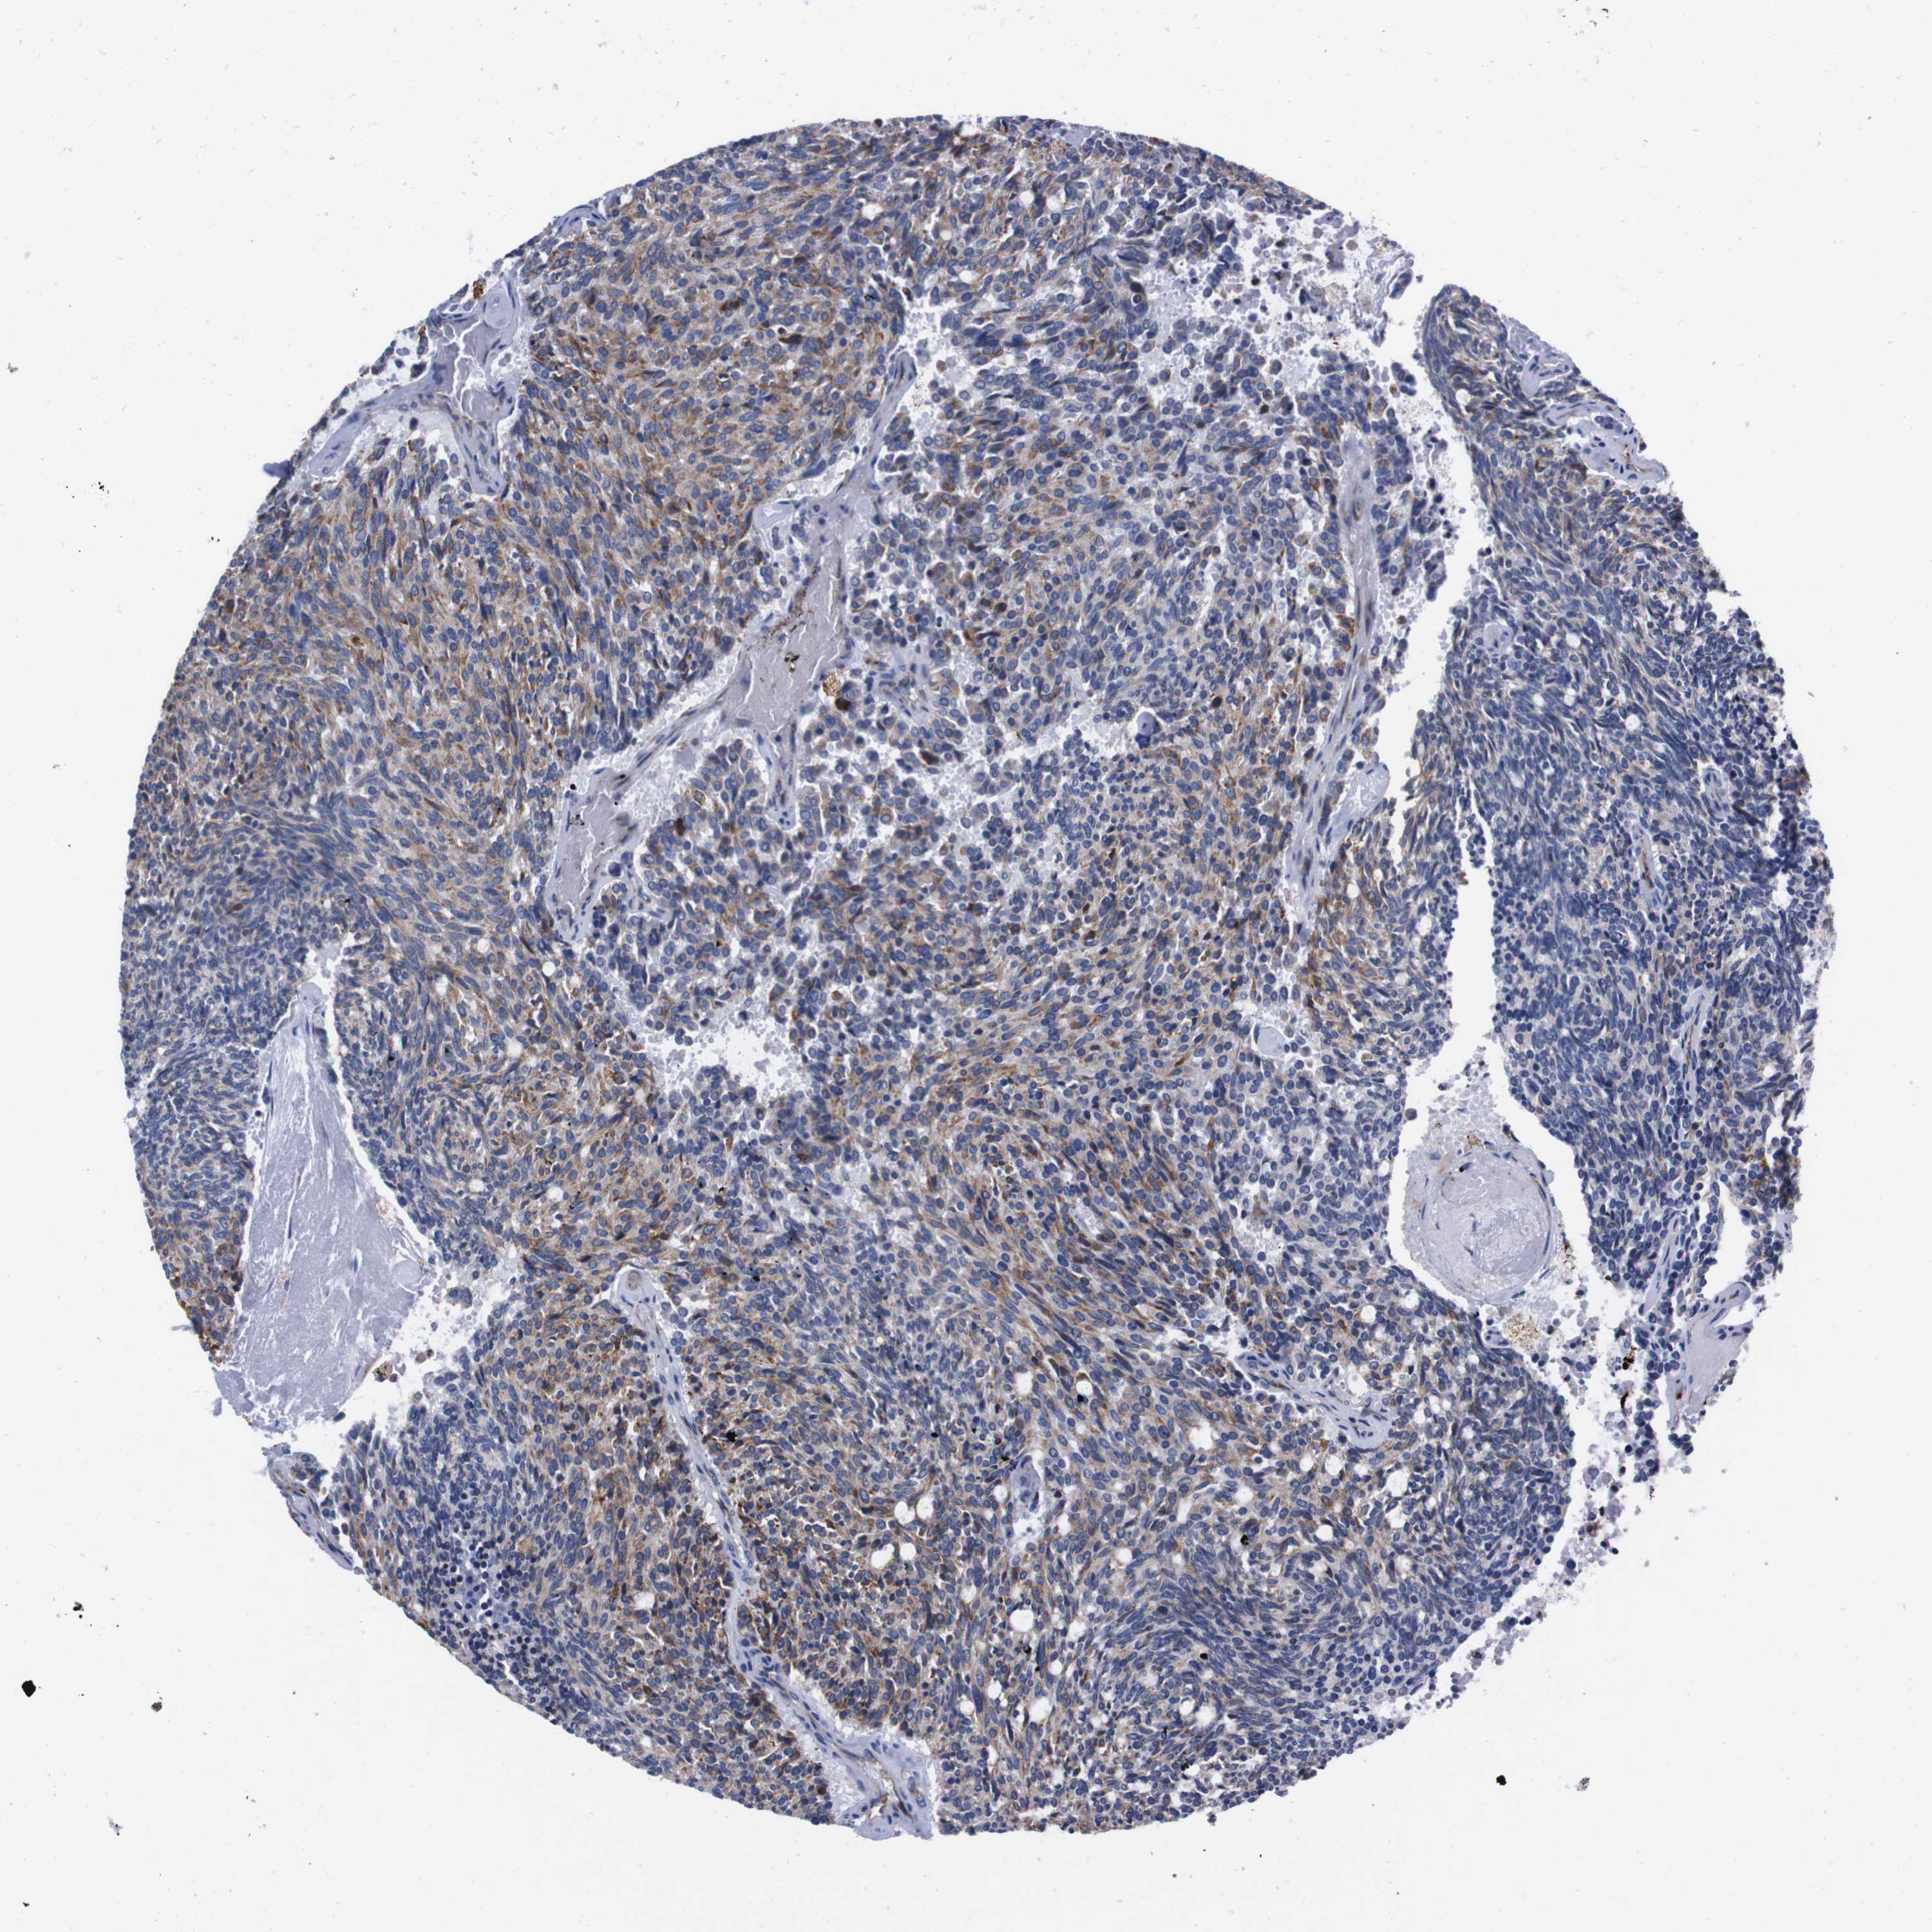

CARCINOID - Protein expressioni

A mouse-over function shows sample information and annotation data. Click on an image to view it in a full screen mode. Samples can be filtered based on level of antibody staining by selecting one or several of the following categories: high, medium, low and not detected. The assay and annotation is described here.

Antibody stainingi

Antibody staining in the annotated cell types in the current human tissue is reported as not detected, low, medium, or high, based on conventional immunohistochemistry profiling in selected tissues. This score is based on the combination of the staining intensity and fraction of stained cells.

Each image is clickable and will lead to virtual microscopy that enables deeper exploration of all samples and also displays staining intensity scores, fraction scores and subcellular localization as well as patient and tissue information for each sample.

Antibody HPA013994

Antibody HPA013995

Staining

High

Medium

Low

Not detected

Intensity

Strong

Moderate

Weak

Negative

Quantity

>75%

75%-25%

<25%

None

Location

Nuclear

Cytoplasmic/membranous

Cytoplasmic/membranous,nuclear

Carcinoid, malignant, NOS

Carcinoma, NOS